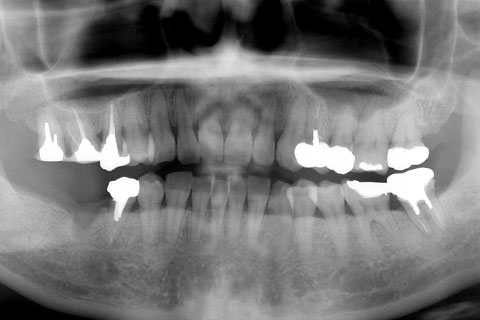

• 症例2

治療前

インプラント埋入時

治療後

年齢・性別

57歳男性

治療期間

3ヶ月

抜歯

なし

治療費

154万円

備考

左上5.6.7 及び左下6.7欠損

治療内容

左上5.6.7と左下6.7欠損部にインプラント埋入

施術の副作用(リスク)

オペによる知覚障害。インプラントによる歯肉炎。インプラント脱落。